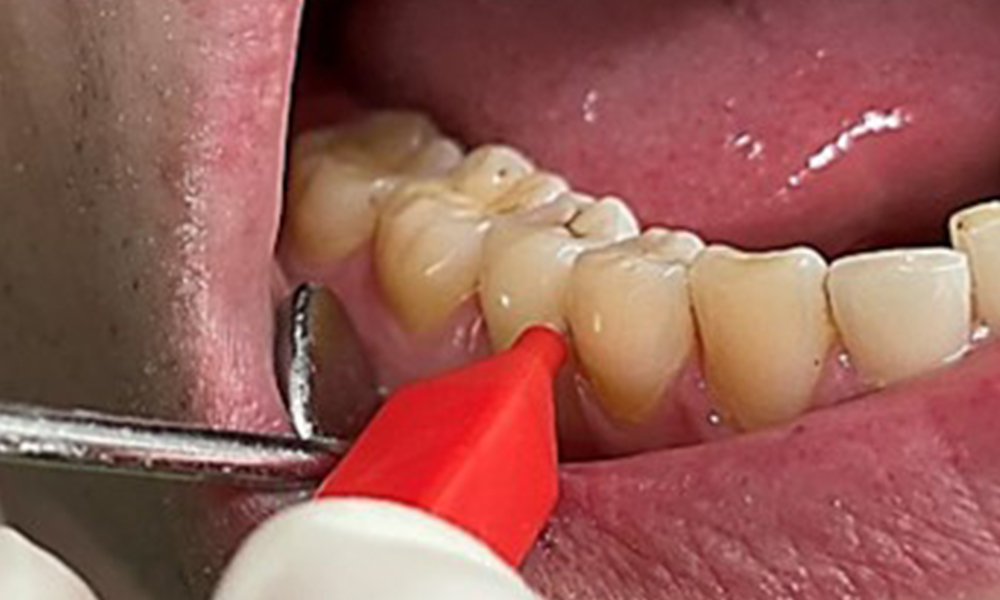

Ziel ist es durch supra- und subgingivale Biofilmentfernung das Erkrankungsrisiko zu kontrollieren. Die Wahl der Instrumente erfolgt

bedarfsgerecht. Zunächst sind Zahnstein und ggf. Konkremente mit Ultraschall und / oder Handinstrumenten zu entfernen (Abb. 10).

Anwendung eines piezobetriebenen Ultraschallgerätes in Rg 36

Abb. 10 Anwendung eines piezobetriebenen Ultraschallgerätes in Rg 36 lingual (hier Proxeo Ultra, Firma W&H), © Dr. R. Krapf